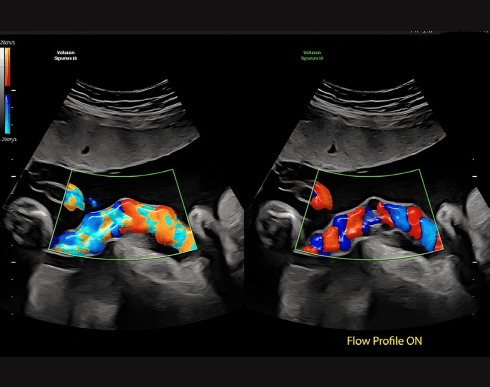

Flow Profiles

Швидко та зручно оптимізує кольоровий та імпульсно-хвильовий допплер.